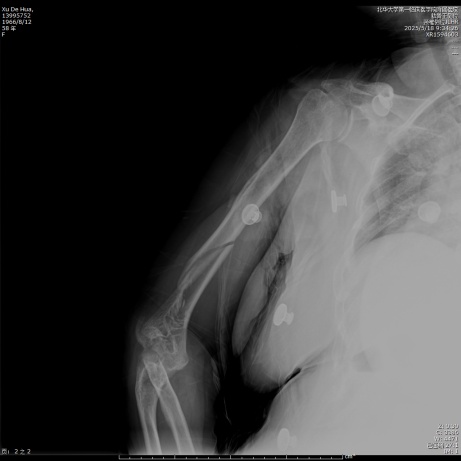

待麻醉生效后,患者取左侧卧位于手术台上,右上肢术区常规消毒,铺无菌单,贴皮肤保护膜。取右上臂中远段后正中入路,纵行切开一长约18.0 cm手术切口,依次切开皮肤、皮下,切开筋膜层,充分显露尺骨鹰嘴,将尺神经分离充分显露后予以保护,应用微型摆锯“V”形截骨尺骨鹰嘴,将尺骨鹰嘴连同肱三头肌腱剥离,湿盐水纱布保护,注意保护桡神经,暴露肱骨中远段,见肱骨中下段螺旋形骨折,分离短缩移位,肱骨滑车、肱骨小头、肱骨内外髁多处骨折线,分离旋转移位,局部骨质缺损,将肱骨中下段、肱骨滑车、肱骨小头、肱骨内外髁骨折复位,克氏针临时固定,后分别于右肱骨远折端内侧、后侧铺放2枚解剖型钢板,注意保护桡神经和尺神经,拧入数枚螺钉固定,C臂透视见钢板及螺钉长度及位置满意(见图2)。并于外髁骨缺损处植入3.0 g β-磷酸钙生物陶瓷不规则颗粒。将截断的尺骨鹰嘴复位后打入两根克氏针临时固定,并应用钢丝“8”字捆绑固定(见图3),活动肘关节,见骨折复位固定确实,关节无异响和绞索。后将尺神经松解前置,见神经松紧带适宜。后清点器械、纱布无误后,冲洗术区,彻底止血,术区留置负压引流管1枚,撒入盐酸万古霉素0.5 g及止血粉于切口内,预防感染及促进止血,应用可吸收性倒刺线2根逐层缝合肌层及皮下,一次性使用皮肤缝合器关闭切口,无菌敷料进行外包扎,石膏托固定肘关节于功能位(90˚屈曲),术毕。手术经过顺利,麻醉效果满意,术中出血量约1200 ml,给予输注ABO血型AB型Rh(D)阳性去白细胞悬浮红细胞2单位,过程中无明显输血不良反应,术后患者呈清醒状态安返病房。

Figure 3. Pre- and post-operative radiographs of double plate and screw internal fixation via the ulnar olecranon osteotomy approach and open reduction

3. 经尺骨鹰嘴截骨入路切开复位双钢板螺钉内固定手术前后X线片